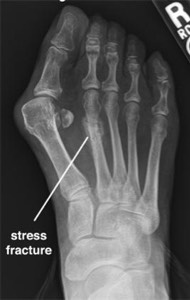

A metatarsal stress fracture is an injury that involves tiny cracks in the bone.